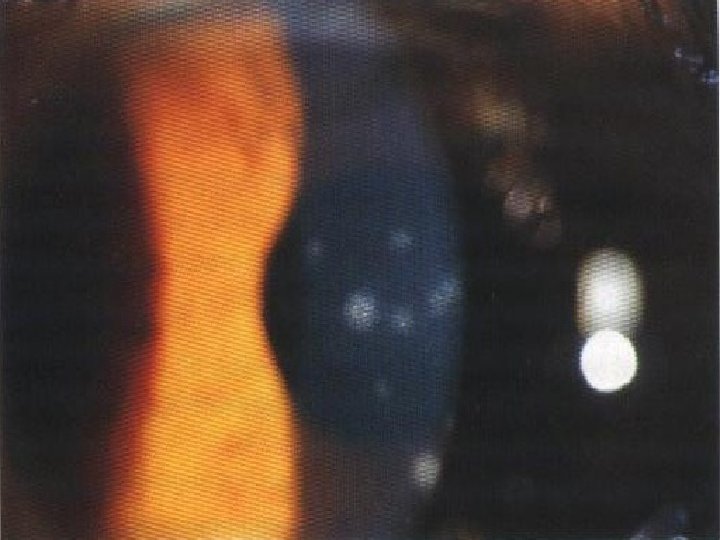

Uveítis Anterior Aguda : Concepto: Inflamación aguda de la capa media del ojo, es anterior cuando está afectado el iris y el cuerpo ciliar. Cuadro clínico: Es generalmente una afección monocular , y se inicia con un dolor de mediana intensidad, vespertino , que aumenta con la palpación del globo ocular, existe fotofobia y lagrimeo, la agudeza visual puede estar disminuida. Signos: Hiperemia cilioconjuntival, reacción ciliar, pupila miótica y perezosa, podemos encontrar precipitados retroqueráticos , hipopiòn , la presión ocular puede estar normal, baja o alta.

Diagnostico diferencial del ojo rojo Diagnóstico Uveítis aguda Conjuntivitis aguda Glaucoma agudo Iris Tumefacto No hay cambios Congestionado, desplazado hacia delante. Pupila Miótica, perezosa e irregular después de dilatar Normal Dilatada, ovalada e inmóvil. Cámara anterior Profundidad normal , presencia de exudados. Normal Poco profunda ó atalamia Córnea Transparente (puede haber precipitados queráticos) Transparente Opaca, edematosa e insensible Hiperemia Ciliar Conjuntival y se acompaña de secreciones Cilioconjuntival Tensión ocular Normal, baja o aumentada Normal Aumentada Dolor Se irradia hacia la frente y se exacerba de noche. Malestar, no dolor Dolor en punzada de clavo , síntomas vagales Visión Disminución de la visión Normal Pérdida brusca de la visión